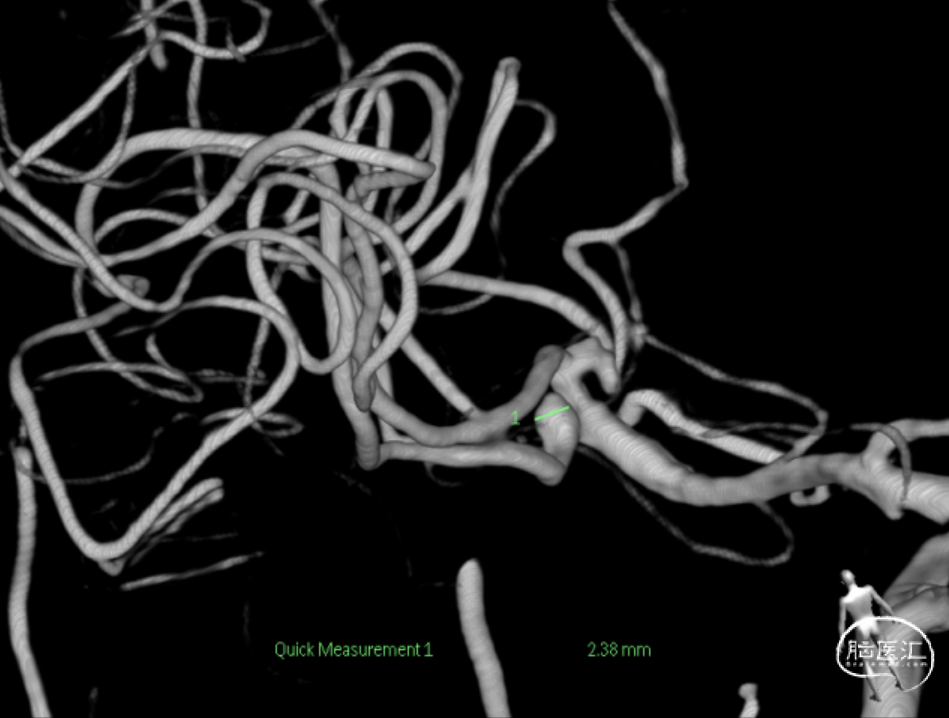

DSA提示近端血管约为2.48mm,远端血管约为1.7mm。